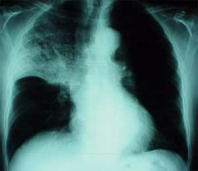

Blutgruppe A hat ein chronisches Schleimproblem, das dauernd für Infektionskrankheiten anfällig macht: Nasennebenhöhlenentzünung, Bronchitis und Lungenentzündung (Pneumonie) etc.

Beispiel: Röntgenbild bei Oberlappenpneumonie mit Verschattung im mittleren bis oberen Lungenbezirk rechts.

-- Lungenentzündung (Pneumonie), Röntgenfoto: http://www.doktor.com/krankheiten/lungenentzuendung.html